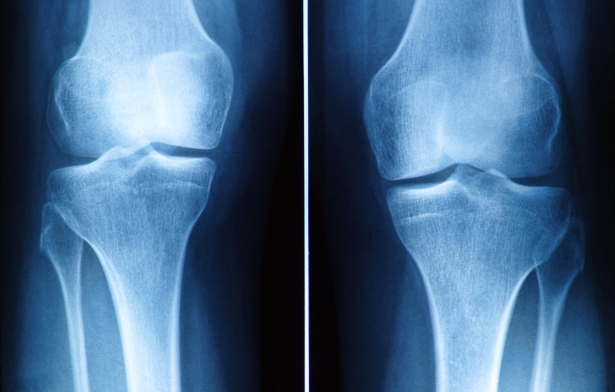

- Chụp X-quang: Giúp bác sĩ quan sát tổn thương xương và sụn khớp.

Chụp X-quang giúp bác sĩ quan sát tổn thương xương và sụn khớp